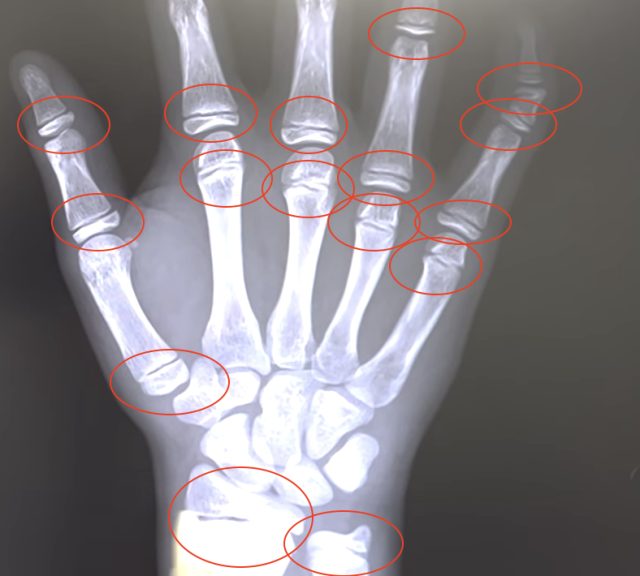

身長先生の最終身長予測は、成長シートだけでなく骨のレントゲンからも診断します。カウンセリングでは、指先のレントゲンから“早熟である”と診断され、最終的には168㎝ほどまで伸びる可能性があるとの予想に。身長を伸ばすために背骨を矯正することの大切さや、まだ治療の余地があること、そのほか厳しい指導も挟みつつも、お母さんの疑問がなくなるまで丁寧に解説する姿が印象的でした。

引用元:東京神田整形外科クリニック公式HP[レントゲンでみる子どもの「骨端線」のイメージ]

(https://tokyo-seikeigeka.jp/column/monitor1)